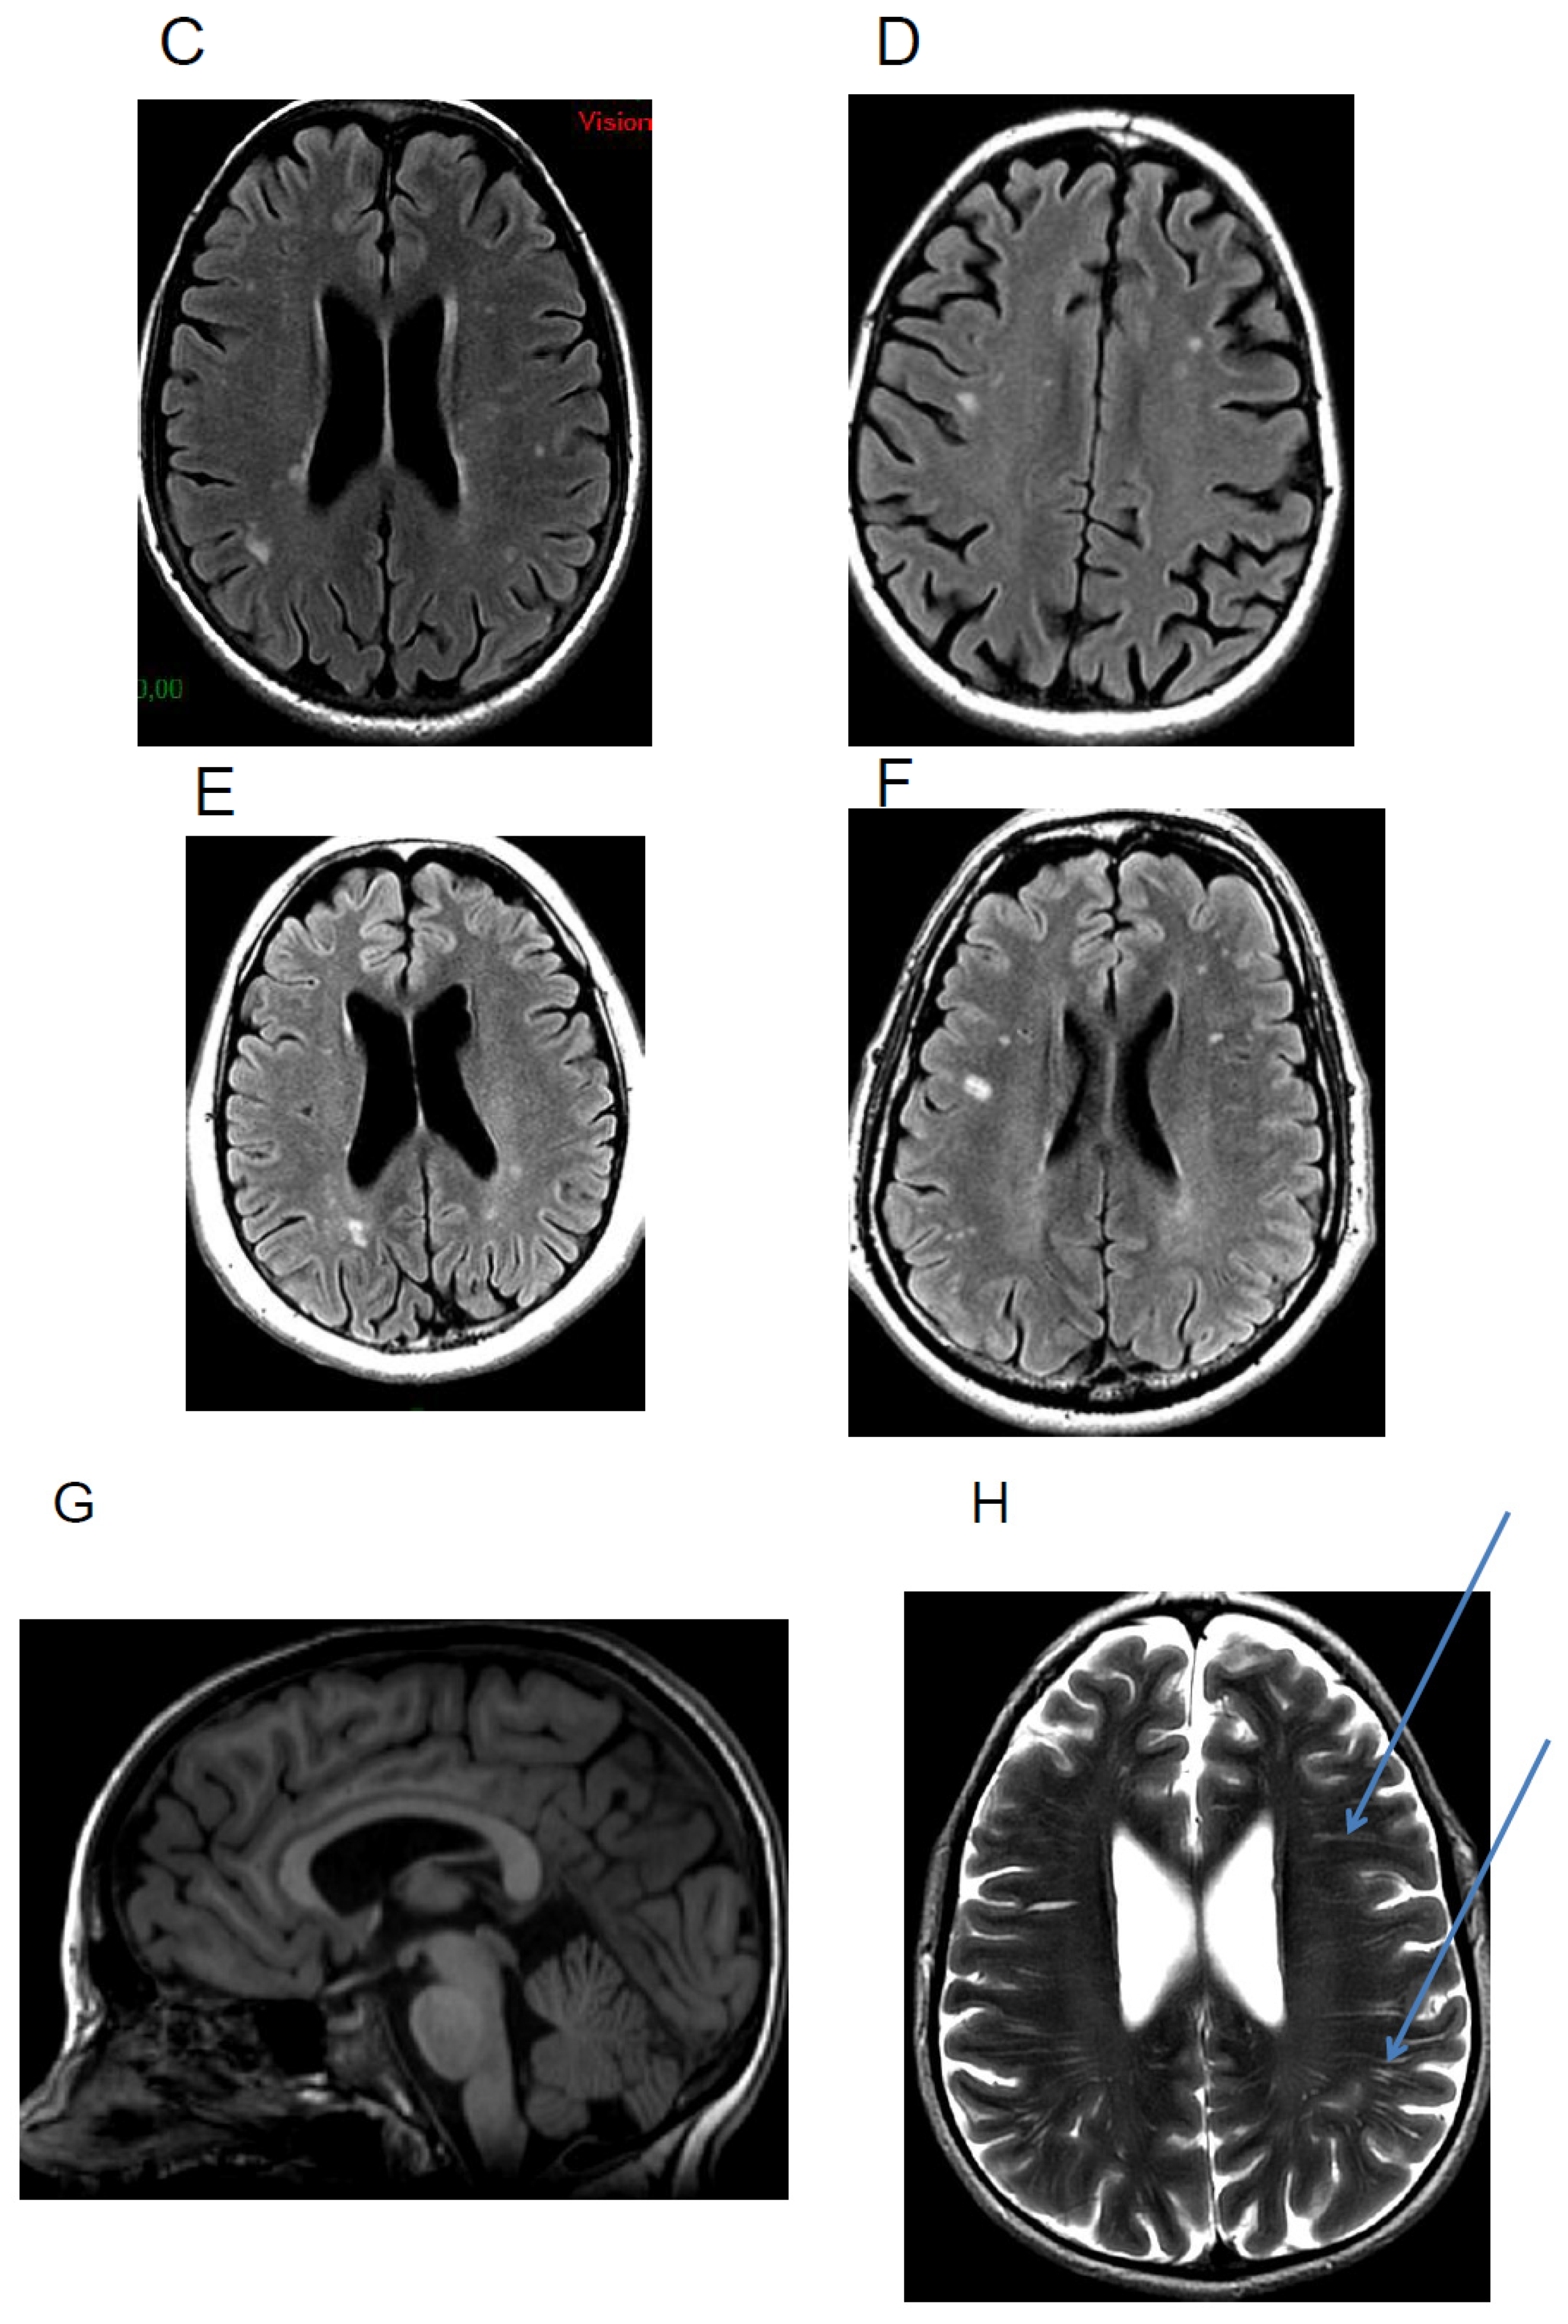

In 2010, Bava et al. studied the cerebral white matter microstructure in 24 young children with cystinosis (age 3–7 years) and examined fractional anisotropy and mean diffusivity [43]. Children with cystinosis evidenced a decrease in fractional anisotropy and a corresponding elevation in mean diffusivity, indicating lower fiber integrity and therefore abnormal anatomical connectivity, in areas of the dorsal visual pathway. This suggests that abnormalities in cerebral white matter are present early on in development [43]. Older cystinosis children (>5 years) demonstrated stronger associations between cystine level and mean diffusivity in bilateral parietal regions, suggesting that, in addition to an early disruption in white matter maturation, there might be a secondary progressive effect of cystine accumulation on white matter organization and connectivity [43]. Recently, using tract-based spatial statistics analysis, we investigated white matter microstructure in adults with cystinosis [17]. Our results showed a significantly decreased fractional anisotropy in cystinosis patients compared to healthy controls in clusters within the corpus callosum’s body, indicating a white matter microarchitecture abnormality, which suggests abnormal anatomical connectivity in this region (Figure 3). This bundle, which plays a central role in inter-hemispheric communication, has also recently been associated with cognitive processes [47,48]. However, controls with nephropathy also present with these abnormalities compared to healthy controls, suggesting that they may not be specific to cystinosis patients.

Figure 3.

Results from tract-based spatial statistics analyses: voxelwise group differences in fractional anisotropy when comparing cystinosis patients and healthy controls. Sagittal, coronal, and axial slices of the tract-based spatial statistics contrasts between cystinosis patients and healthy controls. Red clusters indicate reduced fractional anisotropy in cystinosis patients compared to healthy individuals. Images of contrast are overlaid on a standard Montreal Neurological Institute (MNI) template 1 mm brain and a fractional anisotropy skeleton (in green) with a threshold set to range from 0.2 to 0.8. Tract-based spatial statistics results are thresholded at p ≤ 0.05, corrected for multiple comparisons across space (FWE) using threshold-free cluster enhancement adjusted for age and sex.